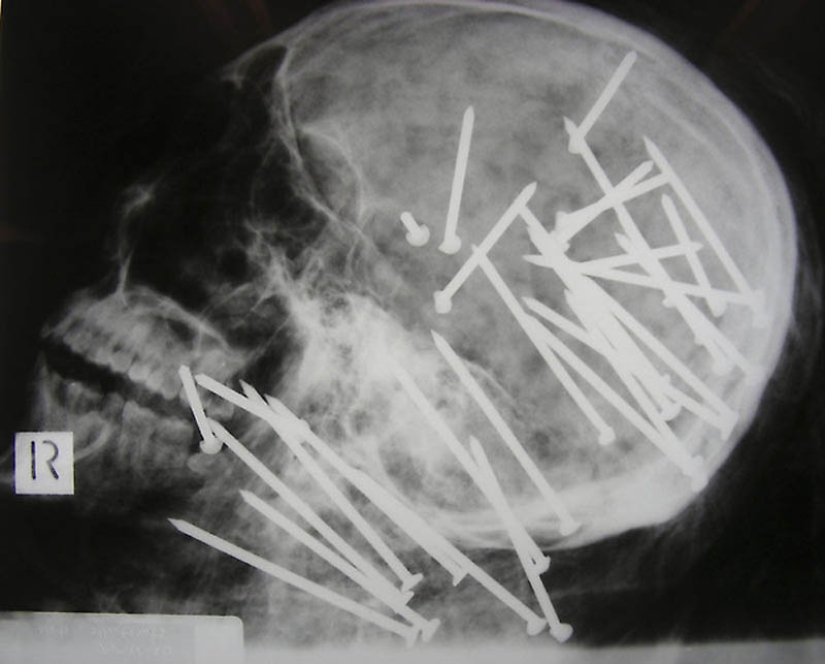

1. The skull of a Chinese man who was shot in the head with a pneumatic hammer